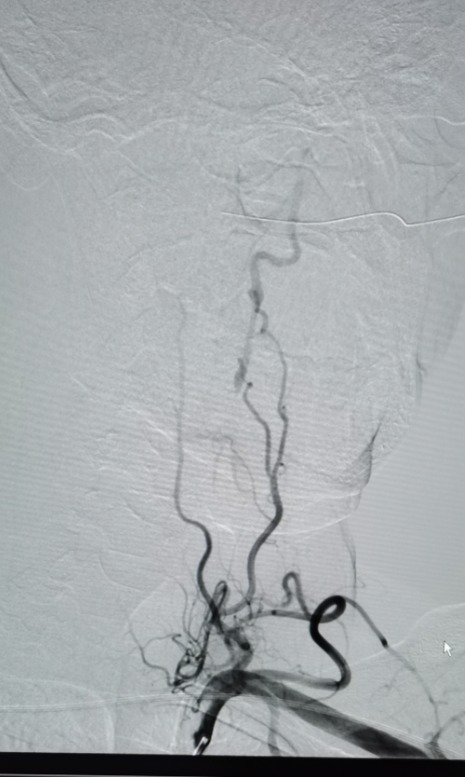

中年男性。因长期头晕,多处求诊均不能明确原因后,来到海南西部中心医院神经内科就诊。经脑血管造影发现患者椎动脉闭塞,右侧椎动脉重度狭窄,小脑、脑干长期缺血。

术前DSA

考虑到患者病情复杂、预期手术难度高、风险大,神经内科介入团队根据实际情况,为患者置入了全国首款maurora雷帕霉素药物洗脱支架。术后造影显示,其右侧椎动脉狭窄解除,脑供血不足明显改善,患者恢复良好。据悉,此次椎动脉药物洗脱支架置入术属我院首次开展,成功填补了海南西部地区脑血管介入治疗的空白。